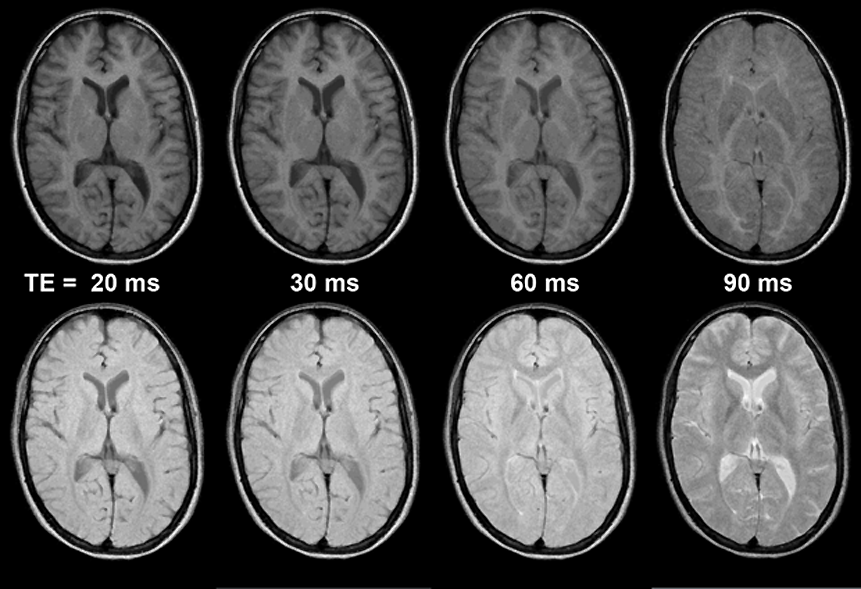

Figura 10-04b:

Spin-echo sequences: Echo times (TE) from left to right: TE = 20 ms, TE = 30 ms, TE = 60 ms, TE = 90 ms. B₀ = 1.5 T.

Top: Short repetition times (TR = 250 ms) emphasize T1-weighting.

Bottom: Long repetition times (TR = 1500 ms) emphasize T2-weighting. In brain imaging, the crossover points of no contrast move to shorter TE values when TR is increased.

Simulation software: MR Image Expert®